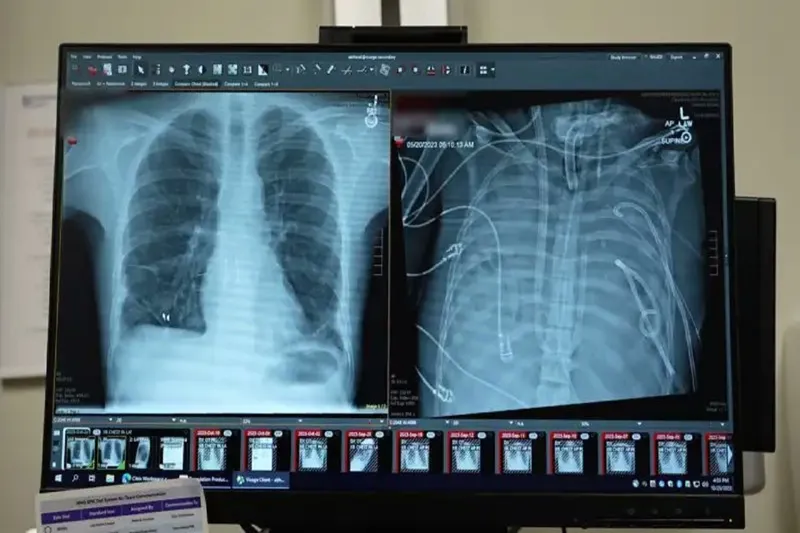

Cerrahlar, akciğerleri geri dönüşü olmayan şekilde hasar gören bir hastayı, organ nakli yapılana kadar yapay akciğer sistemiyle 48 saat boyunca hayatta tutmayı başardı. Yeni sistemin, kalpten geçen kan akışını sürdürürken kana oksijen sağlayabildiği bild

Tıp dergisi Med’de 29 Ocak’ta yayımlanan çalışmaya göre, doktorlar kanı oksijenlendiren ve kalp dolaşımını destekleyen şantlar, tüpler ve pompalarla özel bir sistem geliştirdi. Uzmanlar, bunun gerçek anlamda bir yapay akciğerin, uygun donör bulunana kadar hastayı yaşatabileceğini gösterdiğini belirtiyor.

Olay, 2023 yılında Missouri eyaletinin St. Louis kentinde yaşayan 33 yaşındaki bir erkeğin influenza B virüsüne yakalanmasıyla başladı. Hastaneye kaldırılan hastaya, antibiyotiklere dirençli Pseudomonas aeruginosa bakterisinin neden olduğu ikinci bir enfeksiyon daha bulaştı. Enfeksiyon kana yayıldı ve bağışıklık sisteminin aşırı tepkisiyle birlikte akciğerler işlevini yitirdi.

Bharat, hastanın durumunun hızla kötüleştiğini belirterek “İyileşmiyordu. Aktif olarak ölüyordu.” dedi. Yapılan moleküler testler, hastanın akciğerlerinin kendiliğinden iyileşmeyeceğini ortaya koydu.

Bharat ve ekibi, COVID-19 ve diğer enfeksiyonlar sonrası akciğer nakli yapan bir merkez olarak biliniyor. Ancak hasta, aktif bakteriyel enfeksiyon taşıdığı için bu aşamada nakil olamıyordu. Aynı zamanda, ağır hasarlı akciğerlerle yaşamını sürdürmesi de mümkün değildi.

Bunun üzerine cerrahlar, hastanın hastalıklı akciğerlerini tamamen çıkararak geliştirdikleri yapay akciğer sistemine bağladı. Sistem, kalbin sağ tarafından alınan kanı bir pompadan geçirerek oksijen ekliyor ve karbondioksiti uzaklaştırıyor, ardından kanı kalbin sol tarafına yönlendirerek vücuda pompalanmasını sağlıyor. Böylece hem kalbin normal işlevi korunuyor hem de dokulara oksijen ulaştırılıyor.

Daha önce doktorlar, ekstrakorporeal membran oksijenasyonu (ECMO) adı verilen dış destek sistemini kullanarak, nakil bekleyen bazı hastaları akciğersiz olarak hayatta tutmuştu. Ancak Bharat, ECMO’nun kalp için yeterli kan akışını sağlamadığı için gerçek anlamda bir yapay akciğer olmadığını ifade etti.

Doktorlar, enfeksiyonun temizlenmesinin haftalar sürebileceğini öngörerek hastayı uzun süre bu sistemle yaşatmaya hazırlanmıştı. Ancak Bharat “Bakteri kaynağı olan akciğerleri çıkardığımızda enfeksiyonun çok hızlı şekilde gerilemeye başladığını fark ettik.” dedi.

Enfeksiyonun temizlenmesinin ardından hasta hemen organ nakli listesine alındı ve kısa sürede uygun bir donör bulundu. Aradan iki yıldan fazla zaman geçtiğini belirten Bharat, hastanın durumunun çok iyi olduğunu vurgulayarak “Kalbi normal, akciğeri normal. Hastanın durumu çok iyi.” ifadelerini kullandı. (İLKHA)